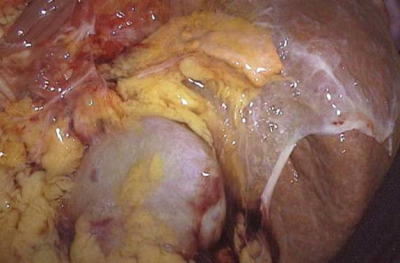

הגישה הכירורגית המומלצת היא הגישה הלפרוסקופית שתוארה. הגישה הבטנית מתבצעת תוך אפשרות להארכת החתך לכיוון החזה - אם השאת גדולה. בדיסקציה יש להקפיד שלא לגעת בשאת. סקירת הבטן, בחיפוש אחר שאתות נוספות, חייב להתבצע כאשר מתרכזים במיוחד בעמוד-השדרה לכל אורכו, באגן, במיטת הכליה וכמובן בצד הנגדי (תמונה 8.14).

הגישה לשאת משמאל כוללת הזזה של הטחול וזנב הלבלב - מדיאלית ומטה - הרמת הקיבה תוך פתיחת האומנטום של הקיבה וכניסה לאמתחת הפדר (Lesser sac). הגישה לשאת מימין מתבצעת על-ידי הזזת הכרכשת בקפל הימני, הזזת התריסריון והווריד החלול מדיאלית.

את הניתוח יש להתחיל בקשירת כלי-הדם המספקים דם ליותרת-הכליה. שאתות גדולות הן לרוב ממאירות ויש לגשת אליהן בחתך בטני-חזי רחב, ולבצע Block resection, הכולל את הכליה, זנב הלבלב, הטחול ושאר איברים נגועים. שיעור התמותה הניתוחית הוא 3% בקירוב.